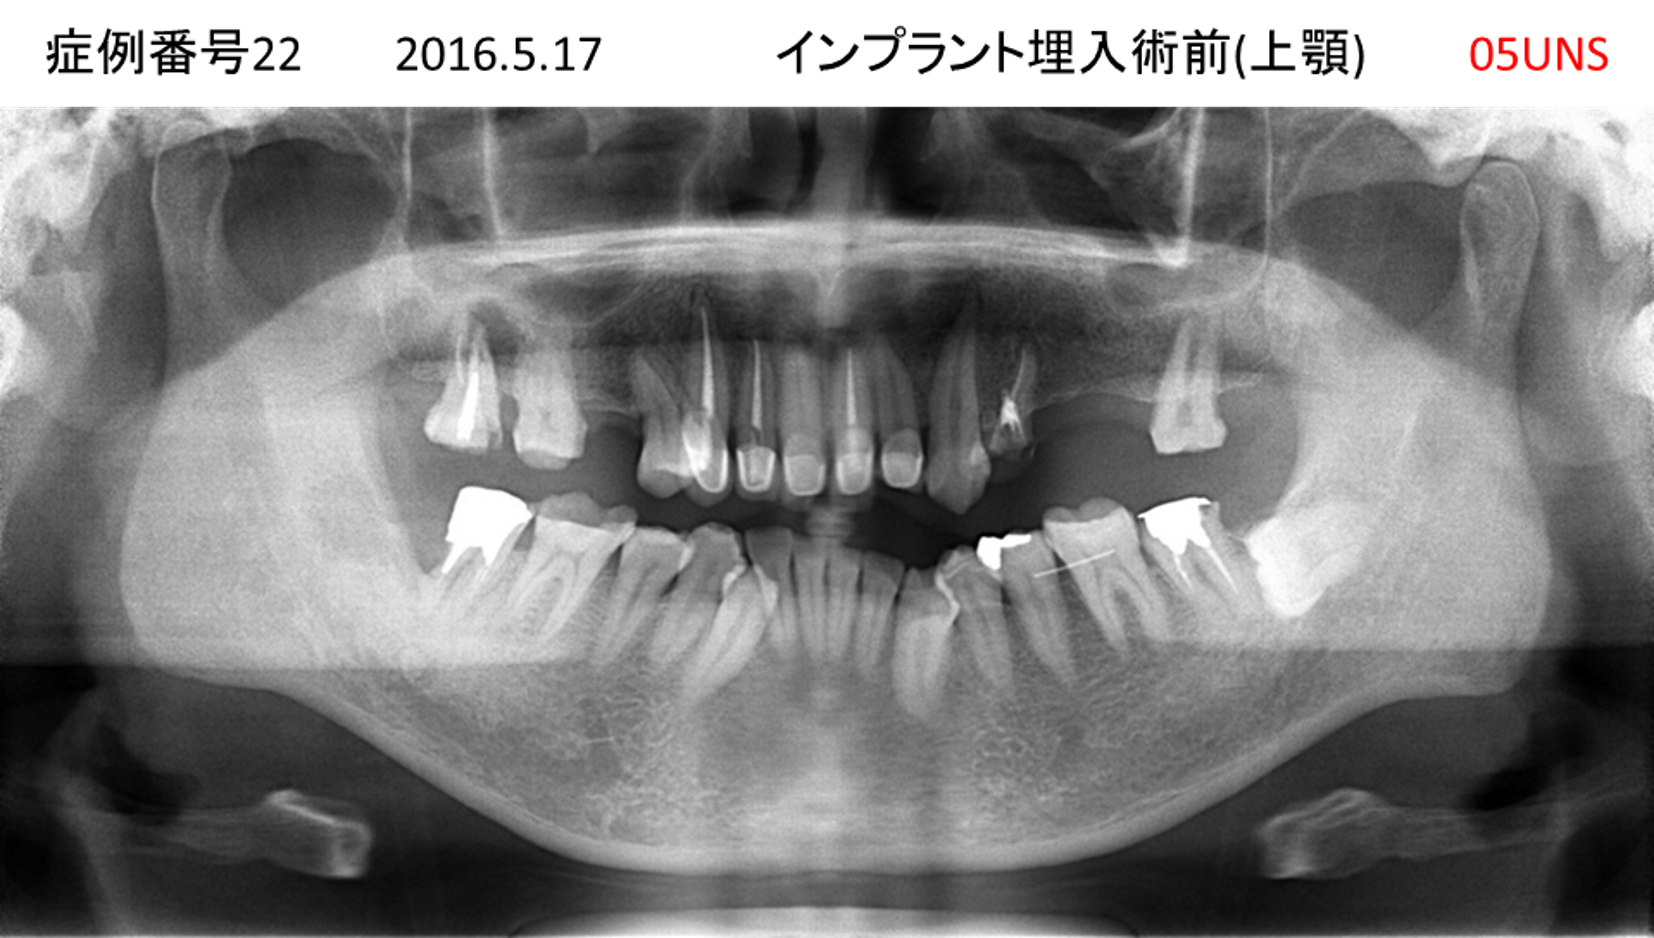

上の前歯が揺れてきてかめない患者様のインプラント症例

| 治療名称 |

インプラント |

| 治療費用 |

440万円+税 |

| 治療期間 |

6か月 |

| 患者さんの症状(主訴) |

上の前歯が揺れてきた。かめない |

| 治療内容 |

サイナスリフト、GBR、インプラント、即時荷重 |

| 治療結果 |

上の前歯の揺れが収まった。奥歯でしっかり噛める。 |

| 治療の注意点(リスク/副作用) |

インプラントが壊れたら再治療が必要 |